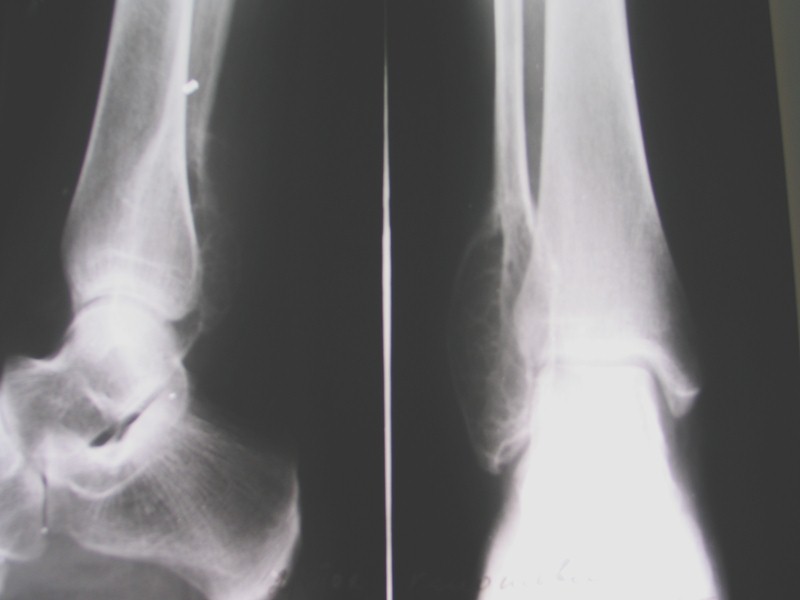

Гигантоклеточная опухоль (Остеокластома) 15% от всех доброкачественных костных опухолей Выявляется в возрасте от 20 до 40 лет Одиночная Преимущественная локализация – метаэпифизы длинных трубчатых костей, реже – кости таза, ниж. челюсть, позвонки Ячеистый тип опухоли – булавовидное вздутие с ячеистой структурой (соты), истончение кортикального слоя, четкая граница от окружающей кости Литический тип – вздутие, полное отсутствие трабекулярного рисунка, дефект кортикального слоя (похоже на метастаз, литическую остеосаркому) Часто осложняется патологическими переломами Малигнизируется часто